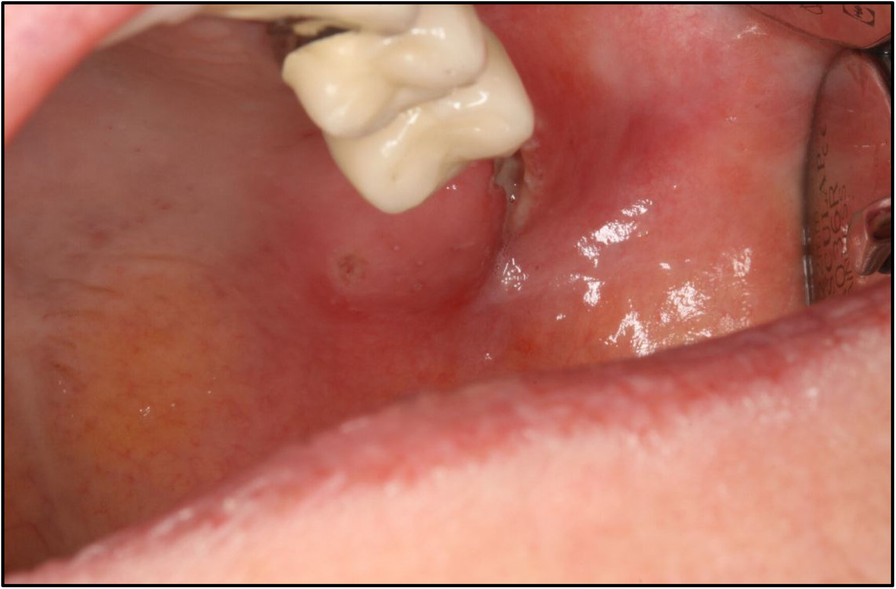

Abscess Lymph Node Neck. there are several types of neck abscesses that are found in children, including the following: Interpret the signs and symptoms that patients with a neck abscess may exhibit. superficial neck abscesses are usually the result of an infection in a lymph node in the neck (lymphadenitis) turning into an. Infections of the lymph nodes in the neck can lead to the formation of abscesses. Determine which patients are most at risk for developing. swollen lymph nodes in the neck can affect children and adults of all ages. lymph node infections: deep neck space infections most commonly arise from a septic focus of the mandibular teeth, tonsils, parotid gland,. a retropharyngeal abscess is a swelling in the neck caused by an infection. It is most often caused by bacteria that can multiply and create a pocket of infection in the interior lymph nodes of the neck. The swelling is usually temporary and harmless.

Infections of the lymph nodes in the neck can lead to the formation of abscesses. superficial neck abscesses are usually the result of an infection in a lymph node in the neck (lymphadenitis) turning into an. a retropharyngeal abscess is a swelling in the neck caused by an infection. swollen lymph nodes in the neck can affect children and adults of all ages. deep neck space infections most commonly arise from a septic focus of the mandibular teeth, tonsils, parotid gland,. there are several types of neck abscesses that are found in children, including the following: Interpret the signs and symptoms that patients with a neck abscess may exhibit. Determine which patients are most at risk for developing. It is most often caused by bacteria that can multiply and create a pocket of infection in the interior lymph nodes of the neck. lymph node infections:

Abscess Lymph Node Neck lymph node infections: a retropharyngeal abscess is a swelling in the neck caused by an infection. Determine which patients are most at risk for developing. deep neck space infections most commonly arise from a septic focus of the mandibular teeth, tonsils, parotid gland,. Infections of the lymph nodes in the neck can lead to the formation of abscesses. It is most often caused by bacteria that can multiply and create a pocket of infection in the interior lymph nodes of the neck. Interpret the signs and symptoms that patients with a neck abscess may exhibit. there are several types of neck abscesses that are found in children, including the following: superficial neck abscesses are usually the result of an infection in a lymph node in the neck (lymphadenitis) turning into an. The swelling is usually temporary and harmless. swollen lymph nodes in the neck can affect children and adults of all ages. lymph node infections: